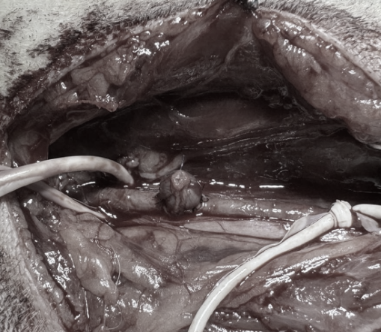

image.png

(E世博(中国)采用手术介入-静脉移植法构建的颈动脉瘤模型示意图)